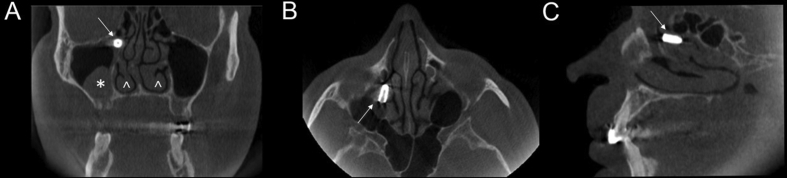

A 63-years-old man was referred to the Department of Otorhinolaryngology for posterior rhinorrhea, a sense of heaviness in the right maxillary sinus and cacosmia. These symptoms started after an oral dental surgery performed 20 days previously, to place an osseointegrated dental implant in the 1.5 upper right molar. The patient did not report headache or any other symptoms suggestive of maxillary sinusitis related to implant dislocation. The patient gave informed, written consent for all the diagnostic and therapeutic procedures, and for the publication of the case report. Clinical examination, carried out under endoscopic 30° (Karl Stortz) view, did not disclose either acute sinusitis, or purulent secretion coming out from the middle meatus, or nasal polyps, or oroantral communication. Considering the disabling symptoms and the progressive worsening, a 3D Cone-Beam Computed Tomography scan (CBCT) was then performed, showing a 10 × 5 mm radiolucency dental implant displaced in the right ethmoidal infundibulum, associated with a mucus retention cyst in the right maxillary sinus and mucosal hyperplasia in the floor of the left maxillary sinus (Figure 1). A functional endoscopic sinusal surgical (FESS) removal of the implant was performed under local anesthesia, using a 30 degree Karl Storz® endoscope with Image One Karl Storz® Camera. Specifically, after removing the horizontal part of the uncinate process with a wide opening of the maxillary sinus, the implant was removed. At the end of the operation, an axorbable oxidized cellulose gauze (Gelitacel®) was applied in the middle meatum without additional nasal packing. The patient was discharged the following day with antibiotic treatment (Amoxicillin/Clavulanate 825 mg/125 mg, 2/day for 6 days). After 3 days, the patient did not report any further symptoms.

Figure 1.

Cone Beam Computed Tomography images in coronal (A), axial (B) and sagittal (C) sections showed the implant (arrow), located at the ethmoidal infundibulum level of the right maxillary sinus. A mucus retention cyst was visible in the right maxillary sinus (asterisk). Notice the asymmetry of inferior turbinates (arrow heads), probably due to compensatory hypertrophy after the right septal deviation.